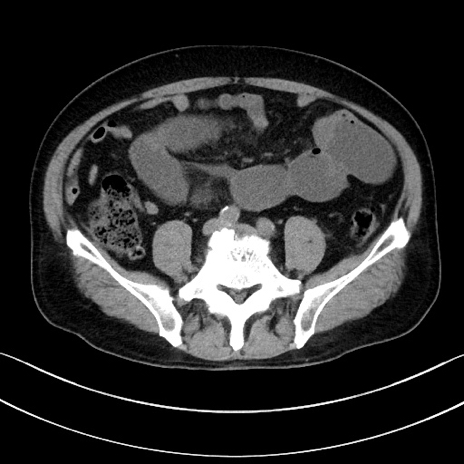

症例15(横断像)

【症例】70歳代男性

【主訴】腹痛

【現病歴】今朝から腹痛あり。全体的に痛い。特に左上の方。排ガスが今日はない。冷や汗が出る。

【既往歴】直腸癌術後

【身体所見】左側腹部〜上腹部に圧痛あり。腹膜刺激症状明らかなではない。軽度反跳痛。左下腹部に術後瘢痕あり。

【データ】WBC 7700、CRP 0.02